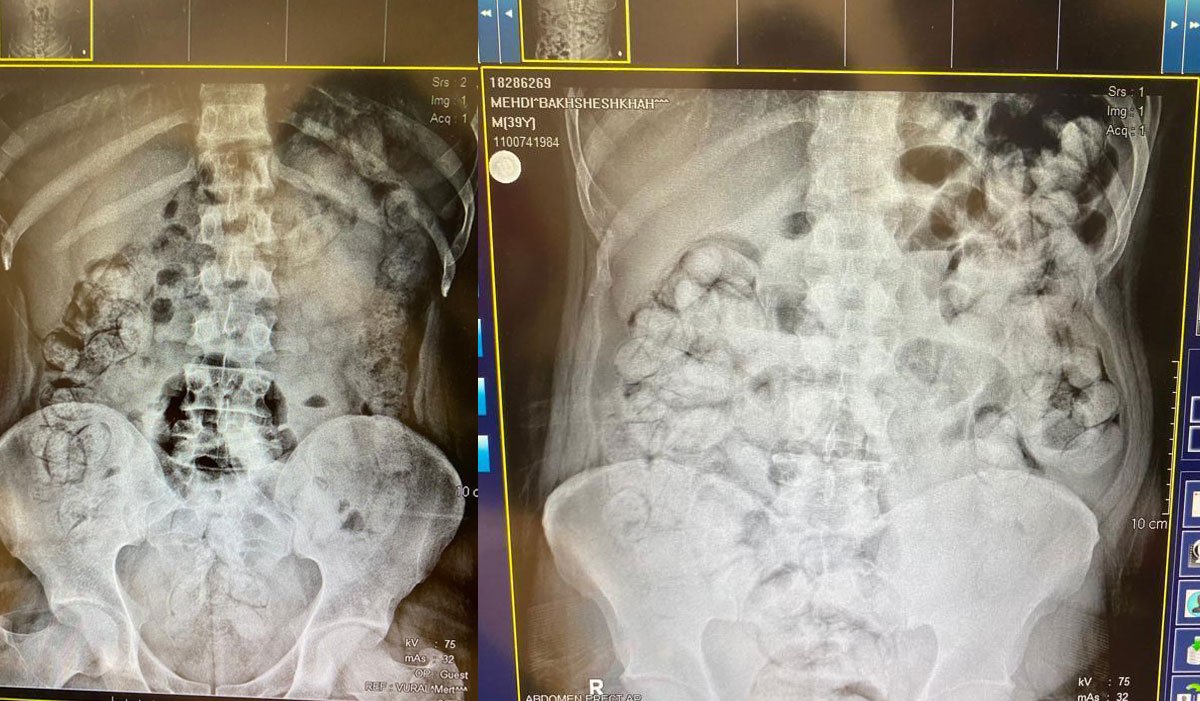

Çekilen röntgen filmlerinde şüphelilerin vücutlarında 62 kapsül eroin ve 210 kapsül afyon sakızı olduğu tespit edildi.

Röntgen çekimlerinde uyuşturucu kapsüllerinin şüphelilerin neredeyse iç organlarının her tarafına yayıldığı belirlendi.

Doktor ve polis, vücutta tek seferde bu kadar yüklü miktarda uyuşturucu görmenin şaşkınlığını yaşadı.

Gözetim altına alınan ve röntgenleri çekilen şüphelilerin vücudundan parça parça "dışkılama" yöntemi ile uyuşturucular çıkarıldı.

Yapılan kontrollerde ve röntgen çekimlerinde, şüphelilerin vücutlarından 411 kapsül afyon sakızı olduğu belirlendi.

Doktor nezaretinde 5 gün süren "dışkılama" yöntemiyle vücutlarından 6 kilo 955 gram ağırlığında 683 kapsül uyuşturucu çıkartılan 5 şüpheli, emniyete götürüldü.